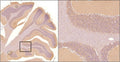

Anti-Alpha Synuclein Antibody (6113-62)

Our Anti-Alpha-Synuclein mouse monoclonal primary antibody from Antibodies Incorporated is produced in-house from hybridoma clone 6113-62. It detects human, mouse, non-human primate, and rat Alpha-Synuclein, and is purified by Protein A chromatography. It is great for use in IHC, ICC, WB.